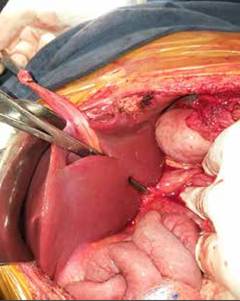

Se realizó bajo anestesia general, con monitoreo hemodinámico invasivo mediante línea arterial, catéter venoso central y sonda vesical. El abordaje a la cavidad abdominal se realizó por laparotomía subcostal bilateral (tipo Chevron), se procedió a la disección del ligamento redondo y de la placa hepática en la cisura de Rex con corte del parénquima hepático (figura 5), se disecó la vena porta izquierda, la cual era de buen diámetro y permeable en los tres casos. Se procedió a la disección de la vena mesentérica superior infra-mesocólica, de buen diámetro y permeable en los 3 pacientes.